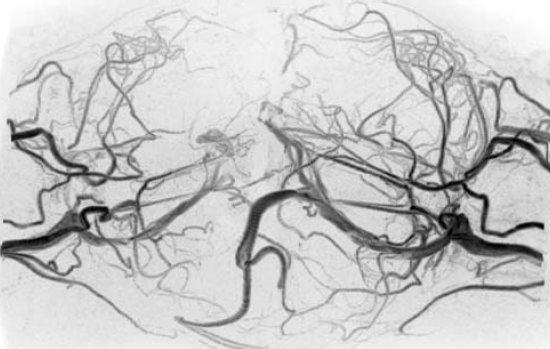

4 ábra.

A második okklúzió utáni kontroll angiográfia.

A februári beavatkozás után 6 hónappal elvégzett kontroll vizsgálat szerint ugyanis a megváltozott áramlási viszonyok miatt új véna, egy belső vénás sinus alakult ki a két összefekvő agyfelszín között, amelyet az orvosok intracerebralis felső sagittalis sinusnak neveztek el. Ez a lelet valószínűleg igen súlyos, esetleg fatális, későbbi intraoperatív vérzéses szövődmény lehetőségét előzte meg. Czeibert Kálmán új módszerével, kifinomul agyi struktúrák különleges megjelenítésével és szerepüknek hangsúlyozásával tehát valószínűleg megmentette az ikrek életét. A második (kiegészítő) occlusiot kizárólag emiatt határozták el és ennek céljából Hudák István és Csókay András ismét Dhakába utaztak és 2018 augusztus 19.-én sikerrel megtörtént a második embolizáció is (4. ábra).

Nem volt könnyű Hudák István dolga. Közel nyolcvan percig kereste az elzárandó eret, amíg megtalálta, majd embolizálta az intercerebralis sinust, valamint a kiegészítő haránt sinus rendszert.